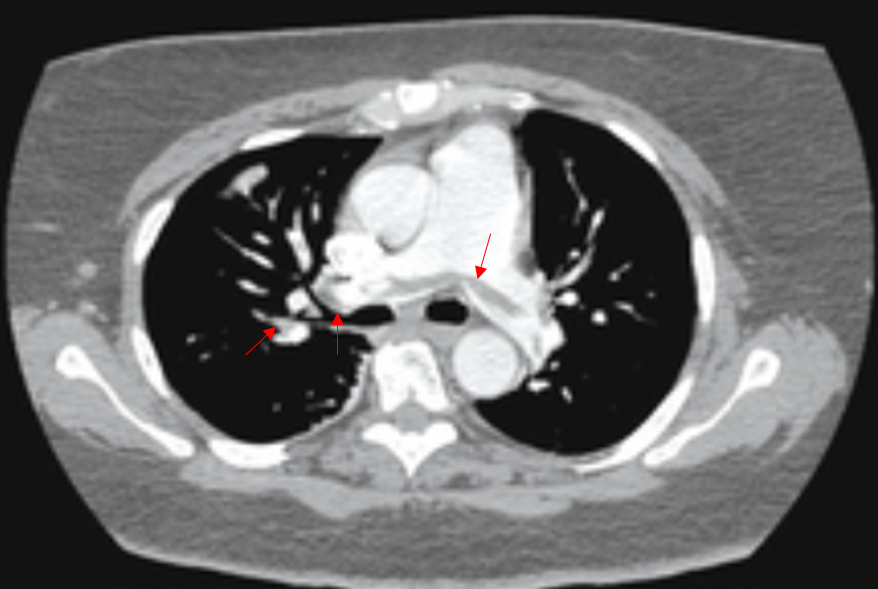

65세 남자가 2일 전부터 숨이 차다며 병원에 왔다. 1주일 전 교통사고 후 침상에서 안정을 취하던 중 3일 전부터 왼쪽 다리가 붓고 아프기 시작하였다고 한다. 혈압 120/90mmHg, 맥박 110회/분, 호흡 22회/분, 체온 36.8℃이다. 신체진찰에서 심음과 호흡음은 정상이다. 가슴 컴퓨터단층촬영 사진과 심전도이다. 치료 방침을 정하기 위한 검사는?

Img | Chest CT: 양측 폐동맥 혈전 |

• CT에서 폐동맥 혈전이 보이므로 폐색전증으로 진단할 수 있다.